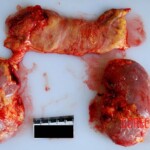

CHINA A young Chinese woman was given the wrong medication and died as a result. A detailed autopsy was performed on her. You can see her individual organs.